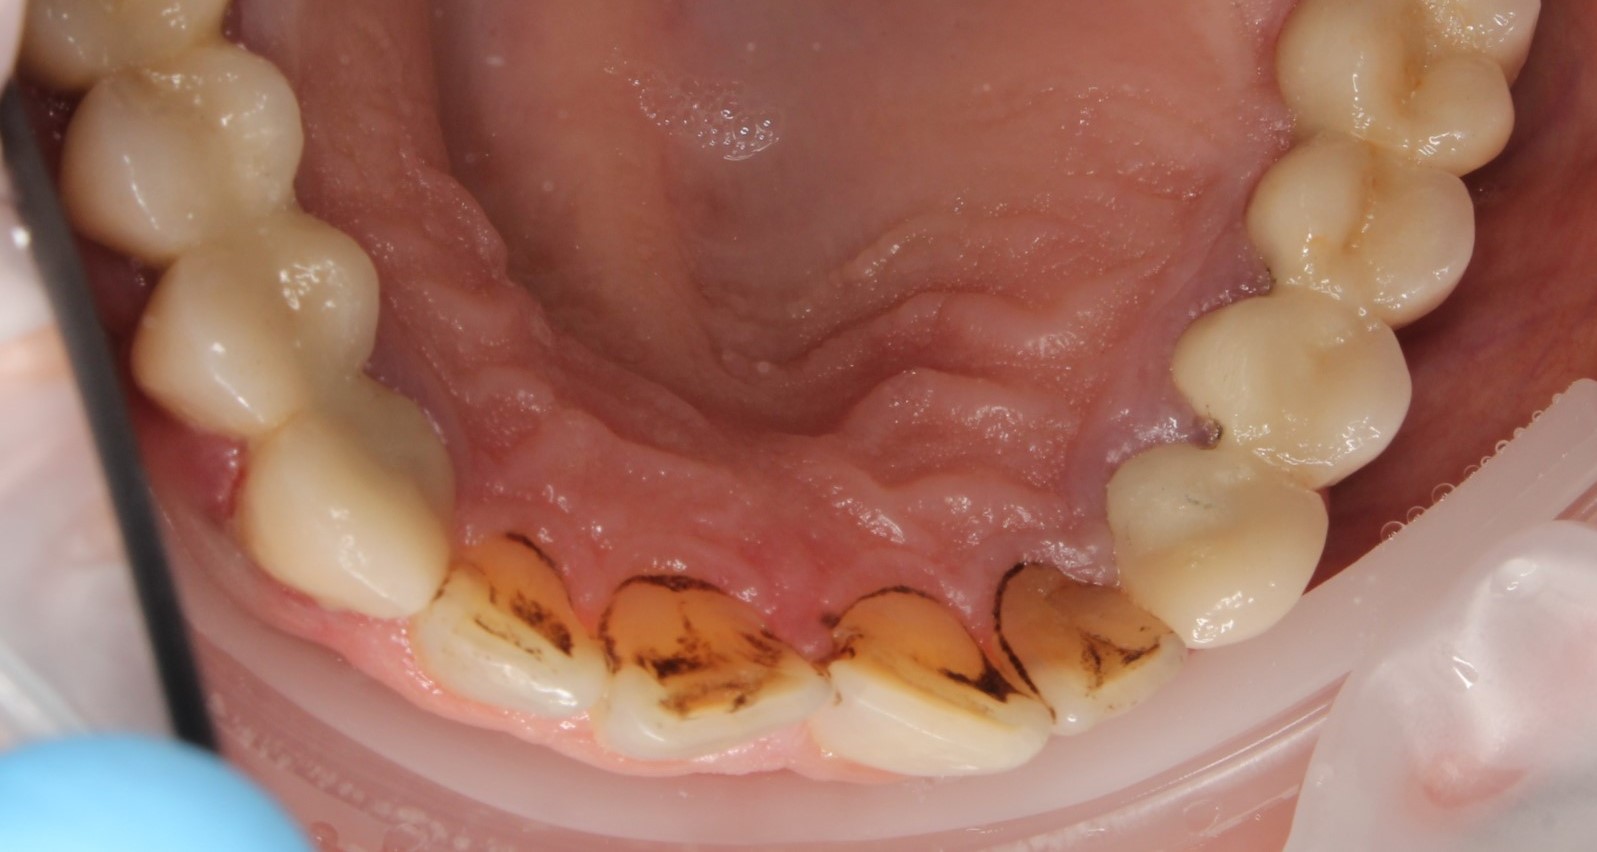

Профессиональная гигиена нижней фронтальной группы зубов

Во время процедуры удален пигментированный зубной налет и камень, проведена полировка зубов.